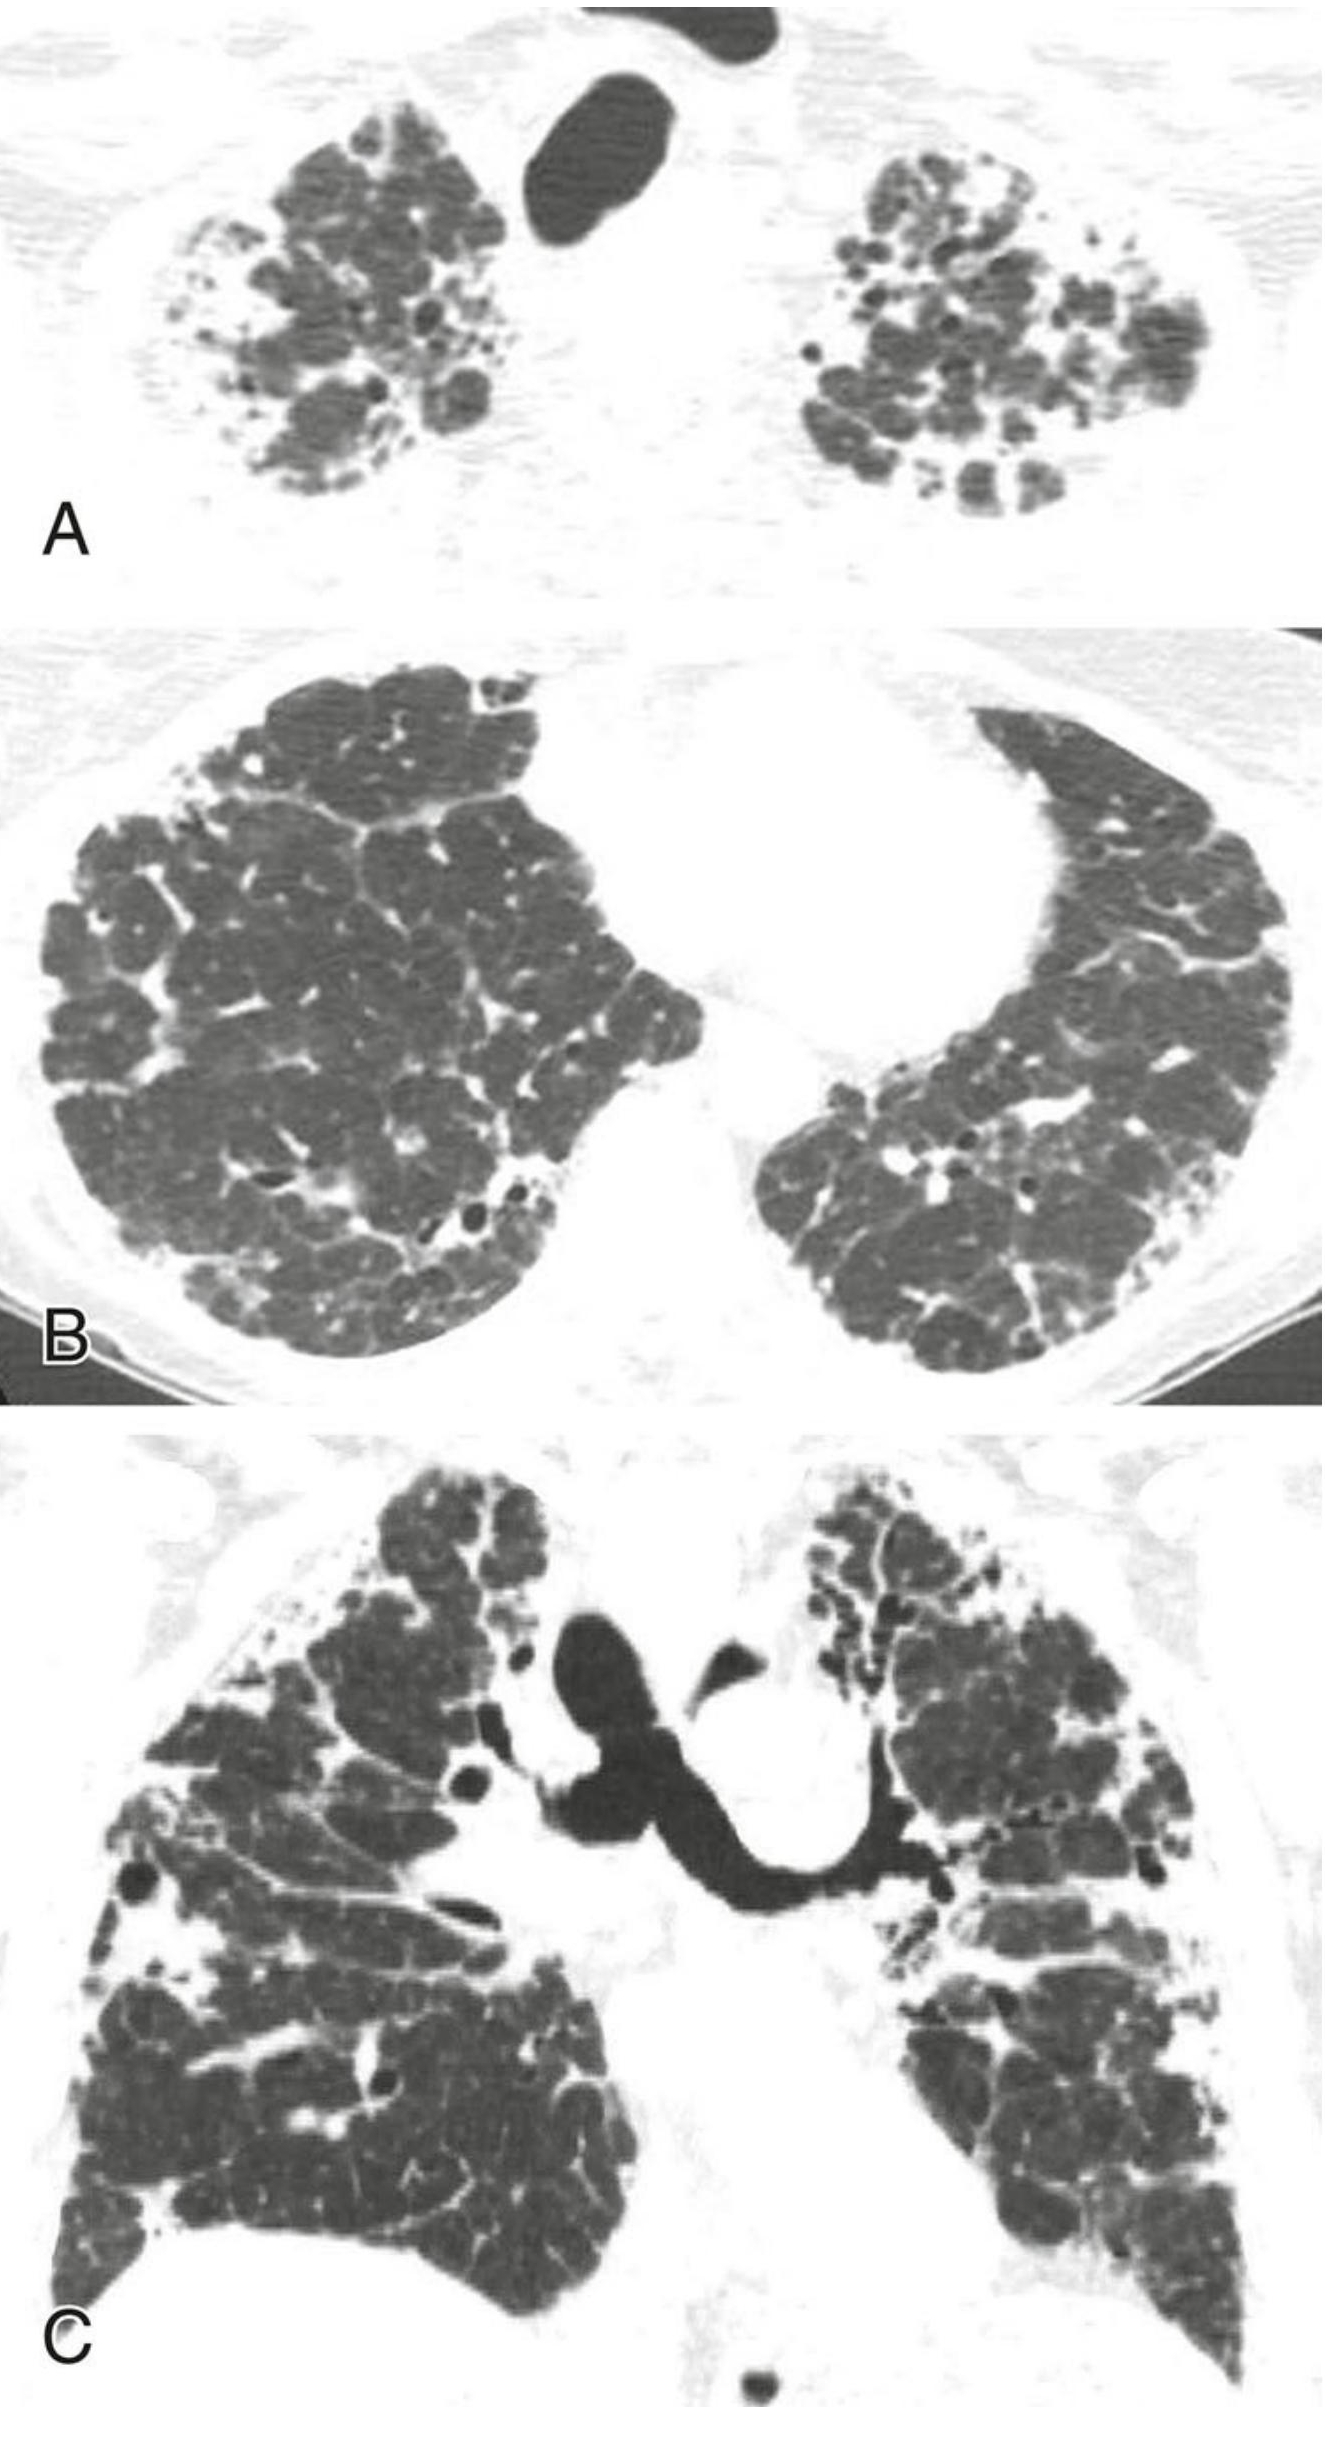

特发性肺间质纤维化(IPF)的典型表现。

上肺(A) 、中肺(B) 、下肺(C)层面的HRCT图像,显示胸膜下和肺基底分布为主的蜂窝征(红箭)和牵拉性支气管扩张(蓝箭),符合普通型间质性肺炎(UIP)。在无已知疾病或接触史的情况下,该患者拟诊为IPF。